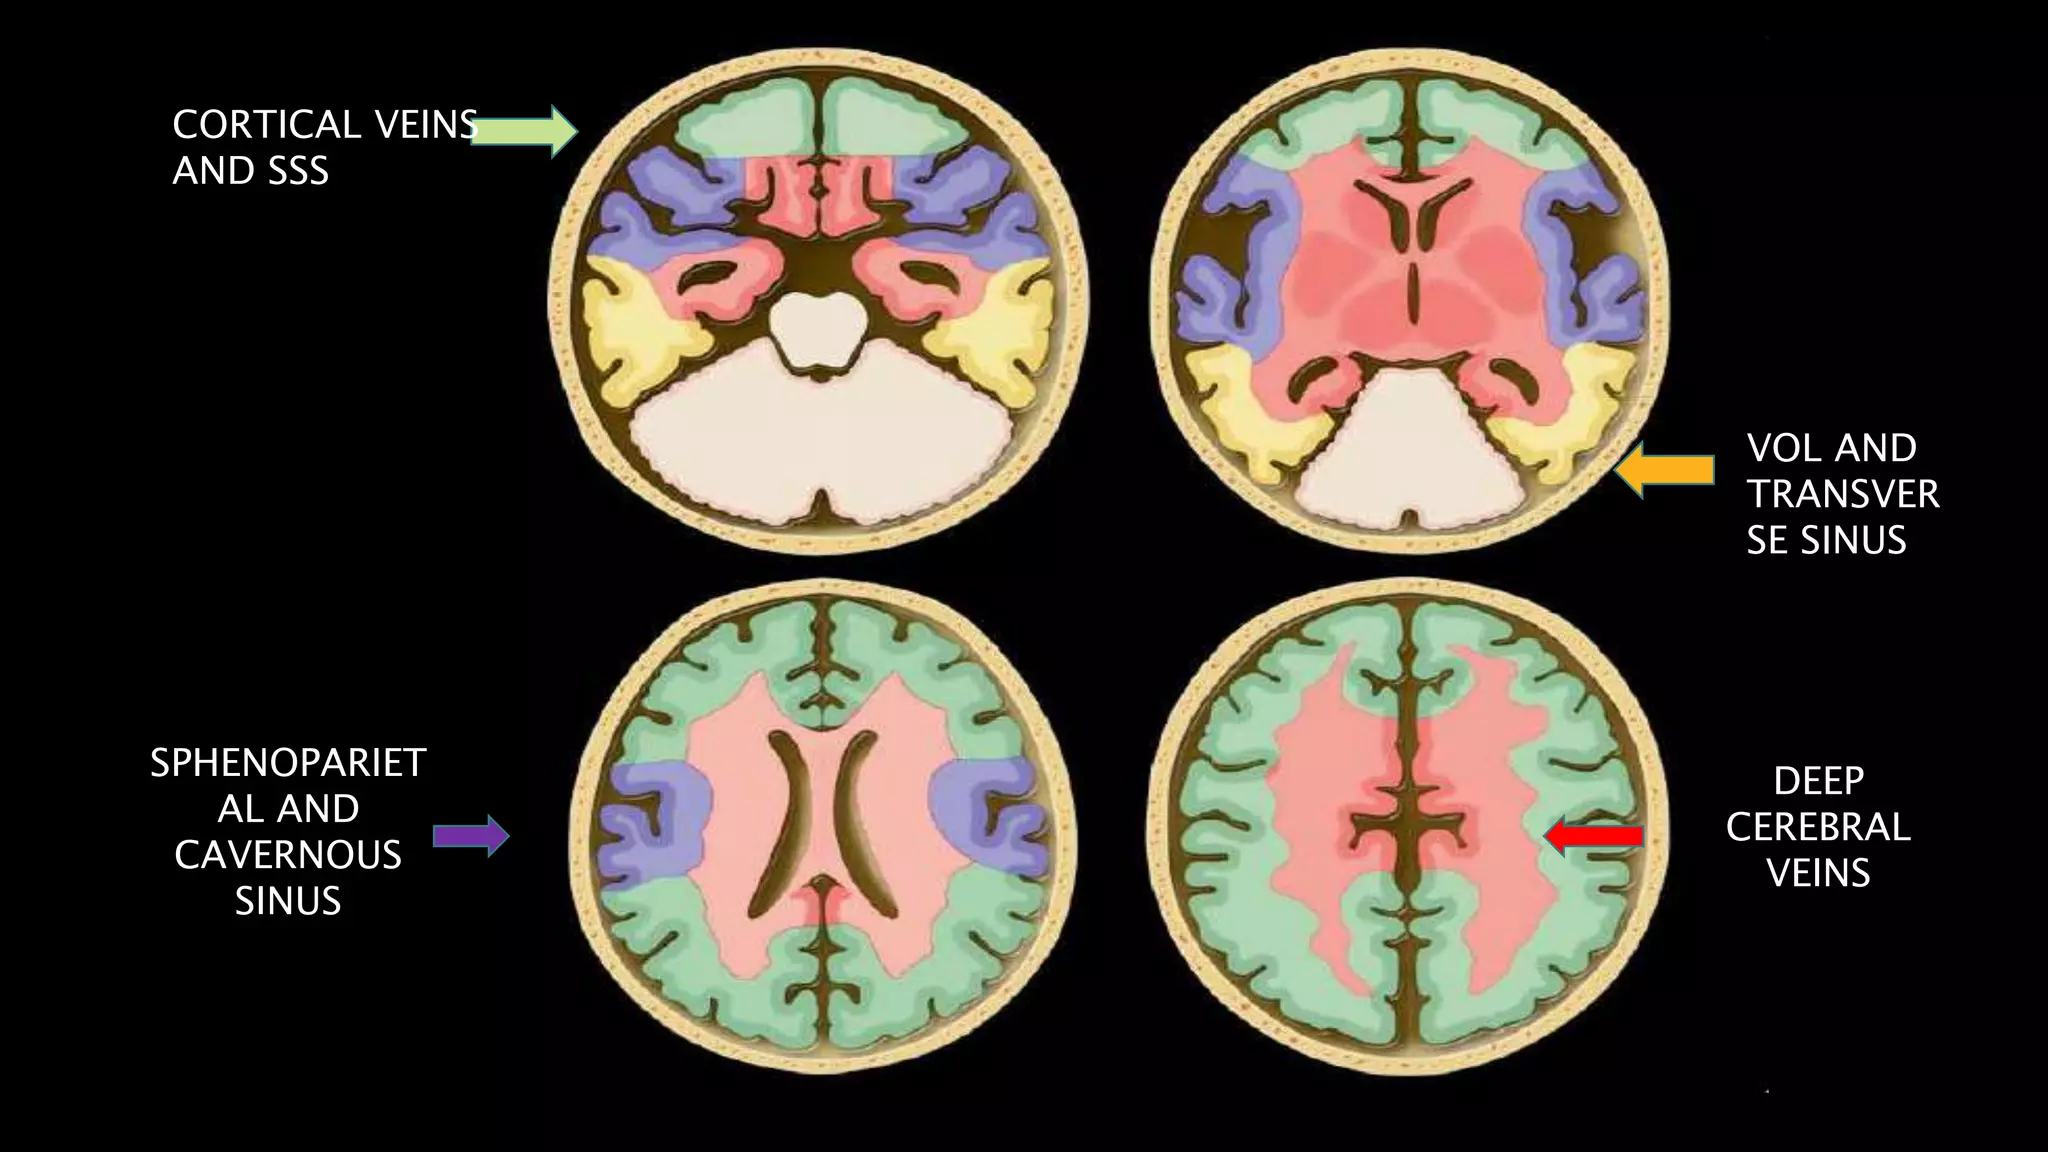

VENOUS

INFARCT

SPHENOPARIET

AL AND

CAVERNOUS

SINUS

DEEP

CEREBRAL

VEINS

VOL AND

TRANSVER

SE SINUS

CORTICAL VEINS

AND SSS

• #130 These are the Axial color coded diag demonstrating venous draignage pattern. As we can see Most of the Superficial part of the brain ie. Cortex , subcortical white matter shown in green color atre drained by cortical vein ( including VOT) and sss. Central core brain structures ie basal ganglia , thalami , lat and 3rd ventricles and most of corona radiate are drained by deep venous system ie. ICB , VOG & SS. Transverse sinus and vein of labbe drain the posterior temporal and inferior parietal lobe as shown in yellow color . Sp and cv